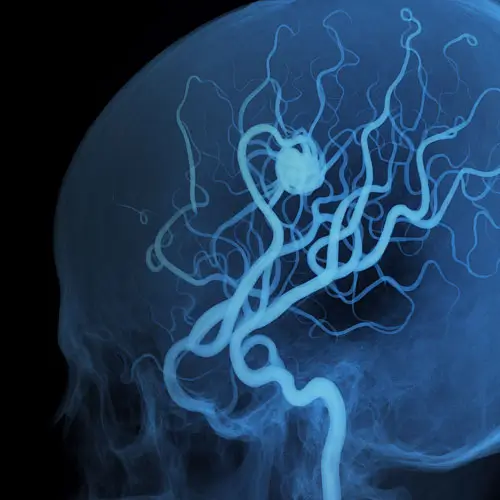

Angiografias Cerebrais

Exame de imagem que permite mapear, com alta definição, as artérias do cérebro e identificar alterações como aneurismas, malformações e estenoses.

Tratamento Endovascular de Aneurismas Cerebrais

Utiliza cateteres para isolar o aneurisma e preservar a circulação, sem necessidade de cirurgia aberta.